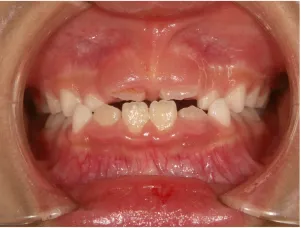

治療中➁小2(7y3m):成長期受け口用ファンクショナルアプライアンススタート

治療中③小2(7y8m):JUMP 受け口が改善

| 行ったご提案・診断内容 | 成長期に行う治療と咬合治療をご提案 受け口用ファンクショナルアプライアンス(写真②③)からスタートし、小2以降で上下顎の拡大・歯列弓の形態修正・前歯の並べ直し(写真④)を行いその後、モノブロック(筋機能的咬合誘導)装置(写真⑤)へ移行し、受け口の再発予防と永久歯を適切な咬み合わせに誘導し、必要によりマルチブラケット法へ移行する治療方法を提案しました。 成長期治療(成長時期にお口の環境を整える治療) 2年生以降から 咬合治療 |

| 治療期間 | 12か月:受け口用ファンクショナルアプライアンス(写真②③) 12カ月:成長期治療の動的治療期間(写真④) 現在、成長の経過観察と咬合誘導中です(写真⑤~⑨) |